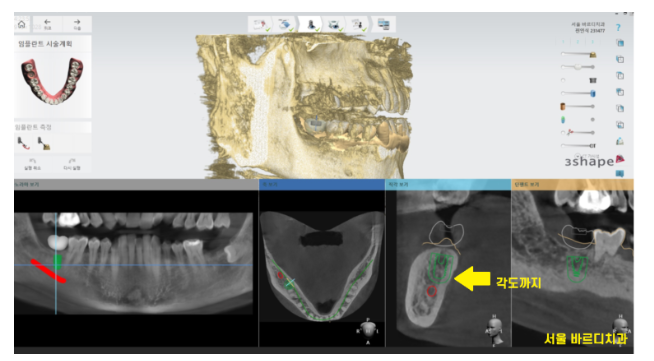

ct를 분석하여

모의 수술을 진행합니다.

임플란트가 들어갈 각도, 사이즈 분석해줍니다!!

보철물이 올라갔을 때의 모습도

예측해볼 수 있는데요.

수술에 필요한 가이드를 제작하여

수술의 정확성을 높여주고 있습니다!

여기서 그치지않고 수술 중간에도 원하는 방향에

제대로 심어지고 있는지

한번 더 확인해줍니다.

3번에 걸쳐서 정확도를 높여줍니다.

1)ct를 통해 1차 분석

2)가이드 제작

3)수술 중 중간 분석

그렇기 때문에 잘못된 방향으로 임플란트가

심어질 수가 없습니다.